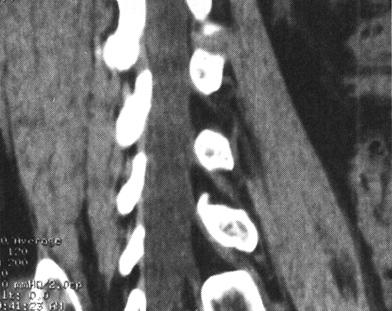

(三)CT

CT的成像过程是用X线束围绕人体某一选定部位做360°的匀速旋转扫描,穿过人体的X线经检测器接收,转变为数字信号经计算机存储、运算并重建为断层图像。螺旋CT扫描是X线球管做连续旋转扫描的同时,扫描床自动匀速水平进床,因此,扫描线在病人的体表上呈螺旋形的。螺旋式扫描与常规CT扫描不同,所获得的是连续层面的信息,是扫描范围内的所有组织的信息,所以又称为体积数据(Volumetric data)。实际上,螺旋扫描所得到的CT图像并不是标准的横断面图像,必需经计算机处理和重建才能获得横断面的图像。病人一次螺旋扫描取得的体积数据允许根据临床需要进行多种方式的重建,如常规层面重建、薄层重叠重建、骨算法重建或软组织算法重建等等。20世纪90年代发展起来的多排螺旋CT,具有扫描时间短(亚秒)、薄层扫描(亚毫米)、重建图像快、多方位多平面三维重建等技术。与单层CT的脊柱常规检查相比,多排螺旋CT可显着地减少扫描时间,由于层面之间的位移被减少到最小,连续成像技术使平面重建成为可能,并减少了伪影的出现。计算机容量的增大和设备软件的开发使得图像的后处理功能更强大、更灵活,特别是仿真技术(Virtual reality)的应用,实现了三维立体(3D-rendering)、伪彩色应用(Pseudocolor)、图像旋转和CT仿真内窥镜(Virtual endoscopy)等重建。

CT在脊柱脊髓损伤中应用很广泛,横断面成像是诊断脊椎骨结构创伤的主要手段,它可显示X线平片不易显示的细微骨折和小关节脱位,并能够很好地显示骨性椎管的情况,可为评价脊髓受压情况提供重要的影像学信息。螺旋CT扫描技术可对患者进行快速连续多部位成像,并支持多平面及三维成像。因而CT扫描对理解脊柱复杂解剖部位,发现细微病变有十分重要的临床意义(图7-4至图7-6)。甚至明显侧弯变形脊柱的冠状面重建亦可通过严格按照脊柱弯曲度改进的软件而获得。单纯轴位扫描很容易漏诊与CT断层面平行的骨折,例如,发生在齿突基部和胸腰水平的创伤,在横断位扫描中不能显示横断水平的骨折线,但在高质量的冠状、矢状和三维的重建图像中显示良好(图7-7至图7-10)。

图7-4 多排螺旋CT重建:沿神经根出口的斜矢状面重建,可显示硬膜囊和神经根管的情况

图7-5 多排螺旋CT重建:冠状面重建,显示硬膜囊和双侧神经根袖

图7-6 多排螺旋CT重建:正中矢状面重建,显示椎体和硬膜囊